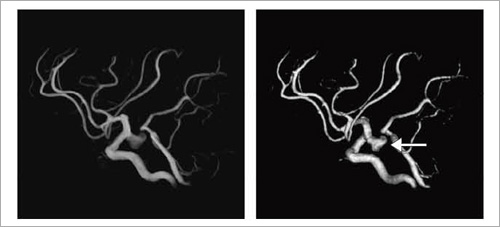

症例2:破裂脳動脈瘤

71歳,女性。意識消失し,倒れているところを発見された。CTにて広範なクモ膜下出血を認め,MRAにて左内頸動脈後交通動脈分岐部動脈瘤が確認された。

MRA,TOF ,TR/TE:21/6.9,FOV:170mm,スライス厚:1.2mm